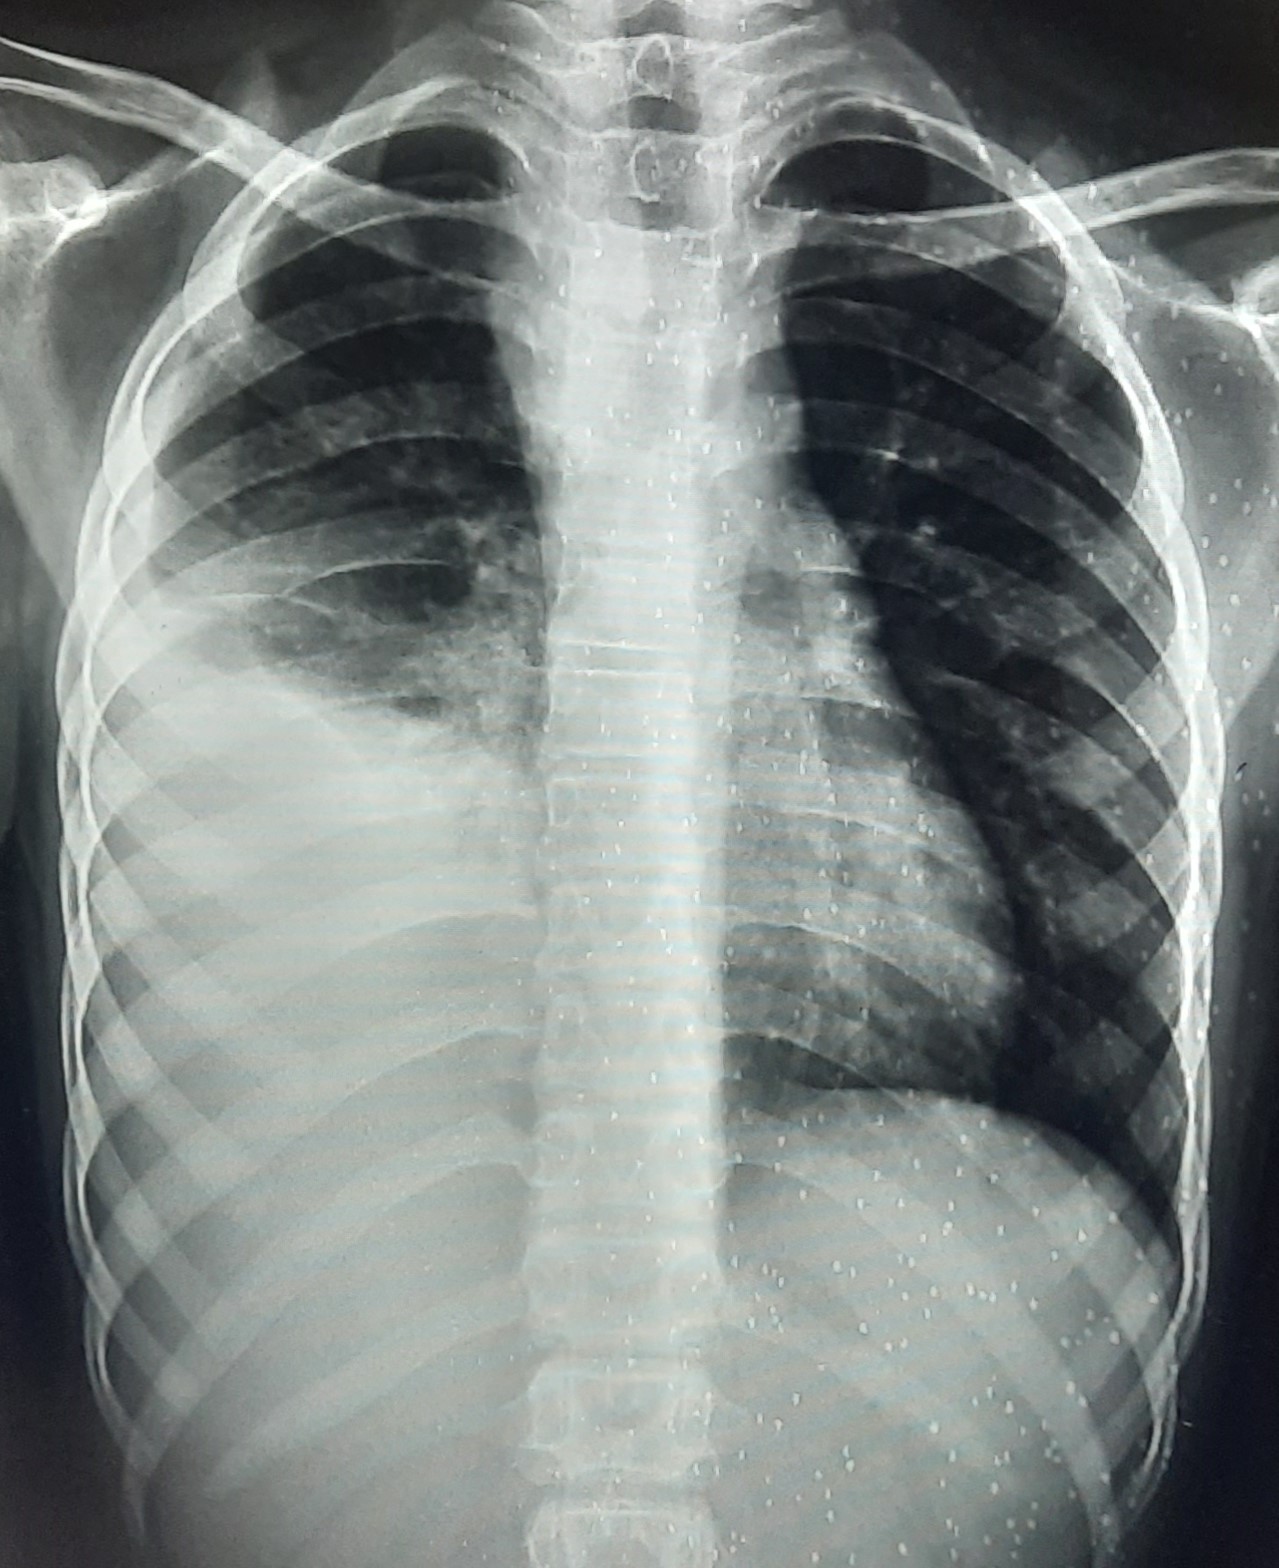

| 271 | IGGMC, Nagpur, Nagpur | P2 | 29-4201 | Abddul Qayyam | Consent taken on Paper | 75 Yrs. |

Provisional Diag : Upper Respiratory Tract Infection

Final Diag : FIBROSIS |

Non-TB Case (Confirmed) | RETICULAR OPACITIES NOTED IN PREDOMINANTLY IN UPPER ZONE OF RIGHT LUNG PARENCHYMA | Abnormality visible on x-ray |